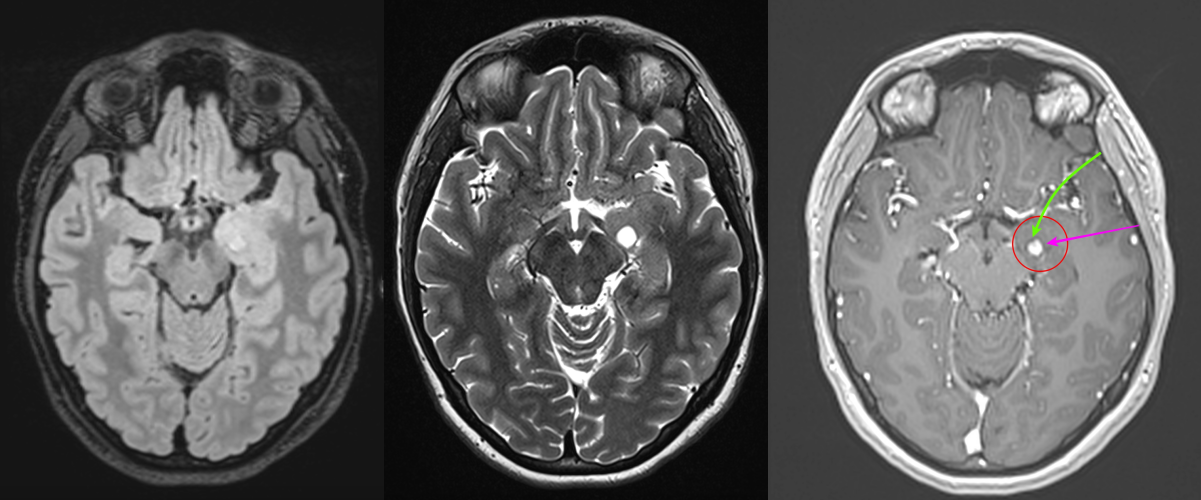

5. Tumora glioneuronală multinodulară și vacuolizantă (MVNT)

- Descoperită recent, frecvent diagnosticată prin RMN.

- Localizare: De obicei lob temporal.

- Aspect imagistic: Leziuni multinodulare neenhancement, bine delimitate.

- Clinic: Epilepsie.

- Tratament: Observație sau chirurgie dacă simptomatică.

- Grad OMS: 1

- Imagistică prin RMN: Aspecte caracteristice (leziuni corticale, fără edem semnificativ, fără contrast intens).